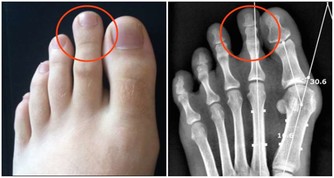

6.皮膚瘙癢,指甲無光:

過於敏感或者皮膚瘙癢是肝硬化的症狀,肝臟疾病在肝臟瘢痕組織形成,血液中膽汁酸的積累會加重你的皮膚敏感和發癢。中醫認為指甲依賴於肝血和肝氣的榮養,肝血虛時指甲上容易長豎紋、凹陷,肝臟排毒不暢時,也會長。這一小細節也許大家都不在意,但是確實肝臟在向你發出最大的信號。